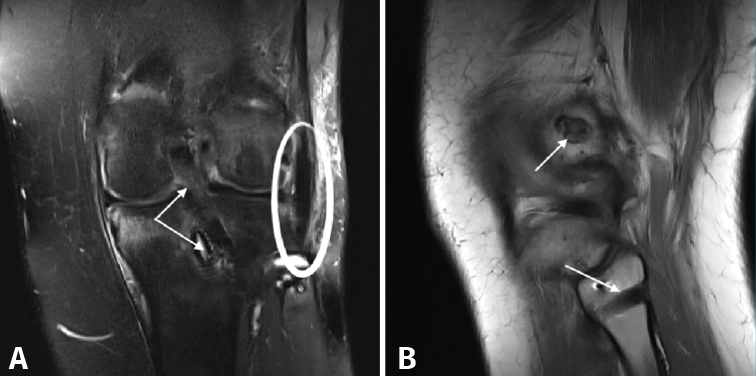

Figura 2. Paciente con lesión KD I (lesión del ligamento cruzado posterior –LCP– y el complejo posterolateral –CPL–). A: corte coronal de resonancia magnética (RM) postoperatoria en el que se muestra la plastia del LCP y el tornillo interferencial de fijación tibial de la misma (doble flecha blanca), así como la plastia del ligamento femorofibular (círculo blanco); B: corte sagital de RM postoperatoria en el que se muestra uno de los túneles femorales para la plastia del CPL (flecha superior), así como el túnel en el peroné para dicha plastia (flecha inferior).